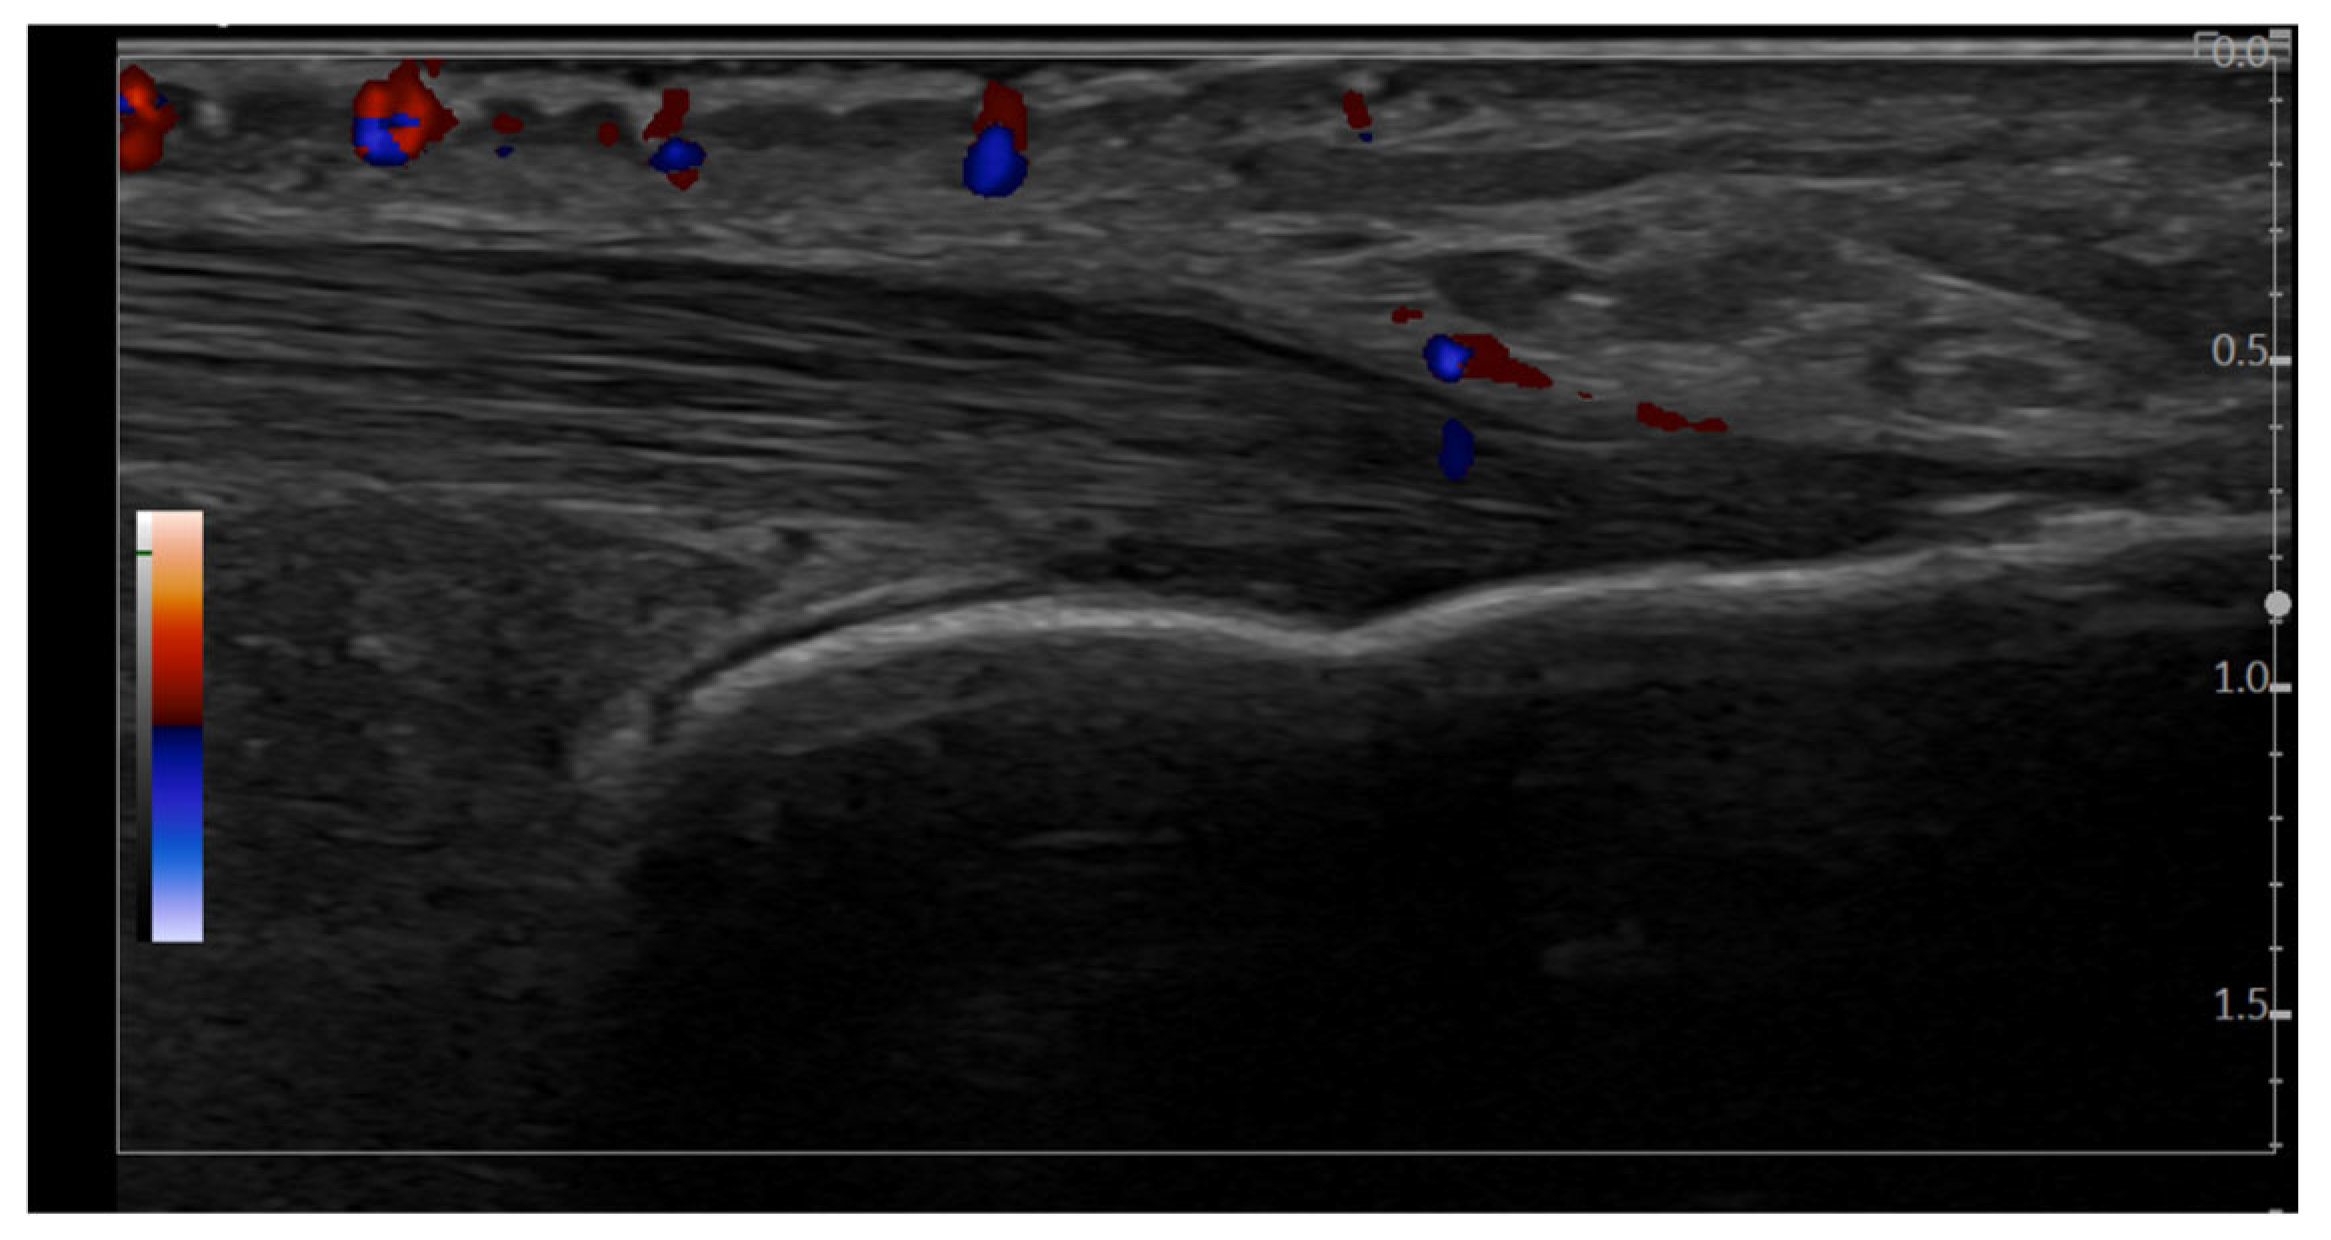

Figure 5. Longitudinal scan, in GS and PD mode, of the Achilles tendon insertion (GE LOGIQ E10 machine, 4–20 MHz linear probe). This conflicting image demonstrates a hypoechoic area at the entheseal level, which meets the GS OMERACT criteria for enthesitis. PD signal appears to be located within the tendon structure (4 evaluators considered it possible inflammatory enthesitis, while 6 evaluators considered it as not being inflammatory enthesitis).